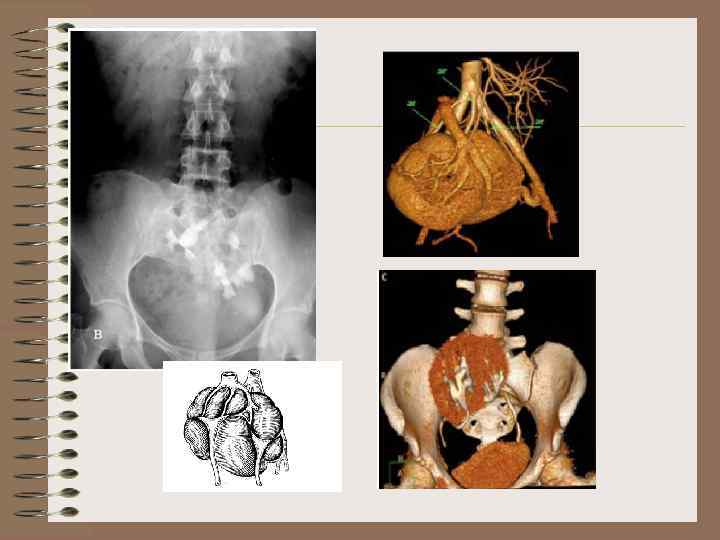

Подковообразная почка • Всегда дистопированная • 90% сращение нижними полюсами • 10% верхними • Лоханки располагаются на передней поверхности

Подковообразная почка Экскреторная урография • Лоханки ниже обычного, могут проецироваться на позвоночник • Продольные оси почек образуют угол, открытый кпереди • Мочеточник короткий

Галетообразная почка • Сращение медиальных поверхностей почек • Располагается по средней линии

S-образная почка • Нижний полюс одной почки сращен с верхним полюсом другой • Ворота почек обращены в разные стороны

L -образная почка • Одна почка в обычном месте, вторая сращена с ней под прямым углом

L- образная почка • Левая почка перемещена вправо • Сращение нижнего полюса правой почки и нижнемедиальной поверхности левой почки